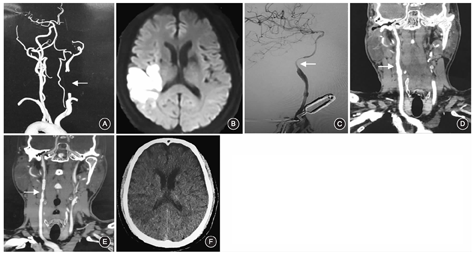

例3男,69岁,主因右侧肢体无力4 d,伴意识不清3 d入院。既往有高血压、脑梗死病史。体格检查:神志朦胧,有运动性失语,双侧瞳孔等大,直径约2.0 mm,对光反射迟钝,左侧肢体肌力Ⅳ级,右侧肢体肌力Ⅰ级,右侧巴宾斯基征阳性。治疗方法同例1。患者未发生围手术期卒中,术后5~7 d复查CTA可见颈动脉斑块切除,血管再通(图3)。术后3~6个月随访,患者仍有运动性失语,右下肢肌力恢复到Ⅳ级,右上肢肌力恢复到Ⅲ级。